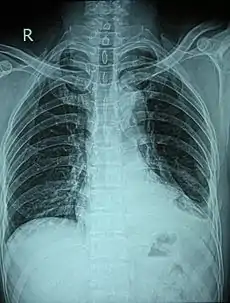

| شکستگی دندههای ۶ و ۷ چپ. | |